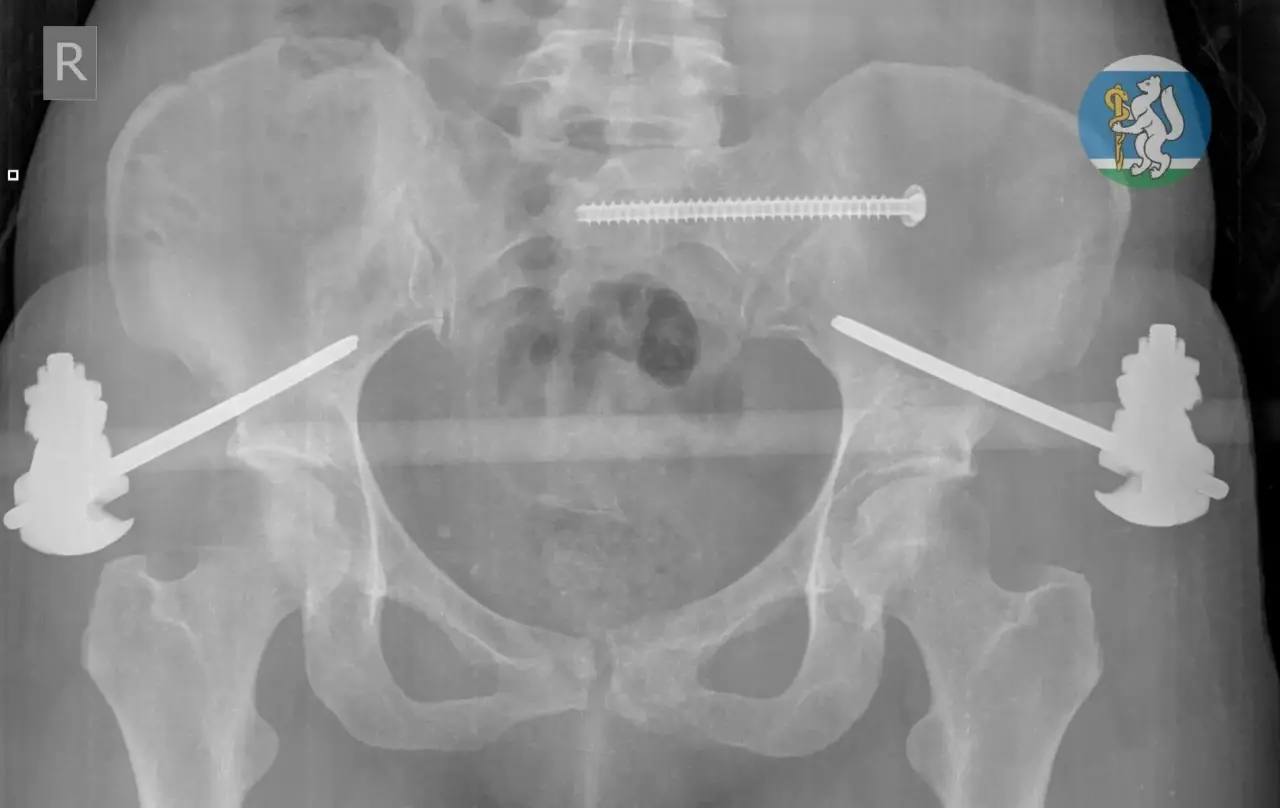

36-летняя жительница Екатеринбурга мыла окна на седьмом этаже и сорвалась вниз. С множественными переломами таза и позвоночника, открытыми переломами ног и тяжелой черепно-мозговой травмой ее доставили в Городскую больницу №36.

Большинство пациентов с такими повреждениями не выживают, но бригада хирургов, травматологов, нейрохирурга и реаниматолога несколько часов боролась за ее жизнь. Спустя месяц после серии сложнейших операций и реабилитации женщину выписали. Сейчас она восстанавливается дома.